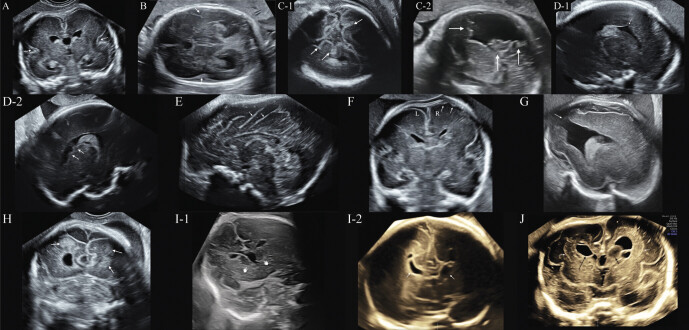

探讨胎儿皮质发育畸形(MCD)超声征象与遗传性MCD的关系。回顾性研究涉及具有以下10种神经超声(NSG)体征之一的胎儿:(A)脊髓裂发育异常;(B)皮质发育里程碑延迟实现;(C)过早出现或异常出现;(D)心室壁边界不规则或心室形状不规则;(E)沟的形状或方向异常;(F)半球不对称;(G)不连续大脑皮层;(H)实质内回声结节;(1)持续性神经节隆起(GE)或神经节空洞;(J)皮质层压异常。95名胎儿参与了这项研究。染色体微阵列(CMA)联合外显子组测序(ES)检测40例胎儿,CMA异常9例,ES异常22例。C征(7/7,100%)、H征(2/2,100%)、A征(18/19,94.7%)、B征(12/13,92.3%)是导致遗传性MCD概率最高的标志。E号、I号和D号的遗传性MCD发生率为66.7-73.7%。在J、F或G征的胎儿中,只有一个或没有发生CMA+ES。FGFR3、CCND2、FLNA或TSC2突变胎儿的体征具有预期的特征。其他不同基因突变的胎儿表现出几种非特异性NSG体征。NSG可以检测到遗传性MCD的几种可靠信号,不同信号的概率不同。大多数症状与特定基因无关。因此,CMA结合ES是首选。

To explore the relationship between ultrasound signs of suspected fetal malformation of cortical development (MCD) and genetic MCD.The retrospective study involved fetuses with one of the following 10 neurosonography (NSG) signs: (A) abnormal development of the Sylvian fissure; (B) delayed achievement of cortical milestones; (C) premature or aberrant appearance of sulcation; (D) irregular border of the ventricular wall or irregular shape of the ventricle; (E) abnormal shape or orientation of the sulci; (F) hemispheric asymmetry; (G) non-continuous cerebral cortex; (H) intraparenchymal echogenic nodules; (I) persistent ganglionic eminence (GE) or GE cavitation; (J) abnormal cortical lamination.95 fetuses were included in the study. Chromosomal microarray (CMA) combined with exome sequencing (ES) was available in 40 fetuses, CMA was abnormal in nine and ES in 22. Sign C (7/7, 100%), sign H (2/2, 100%), sign A (18/19, 94.7%), and sign B (12/13, 92.3%) were the signs leading to the highest probability of genetic MCD. The incidence of genetic MCD for sign E, sign I, and sign D was 66.7-73.7%. Only one or none of the fetuses with sign J, sign F, or sign G underwent CMA+ES. The signs in the fetuses with FGFR3, CCND2, FLNA, or TSC2 mutations had the expected features. The other fetuses with different gene mutations showed several non-specific NSG signs.Several reliable signs for genetic MCD can be detected by NSG, and the probability varies with different signs. Most signs are not associated with a specific gene. Therefore, CMA combined with ES is preferred.